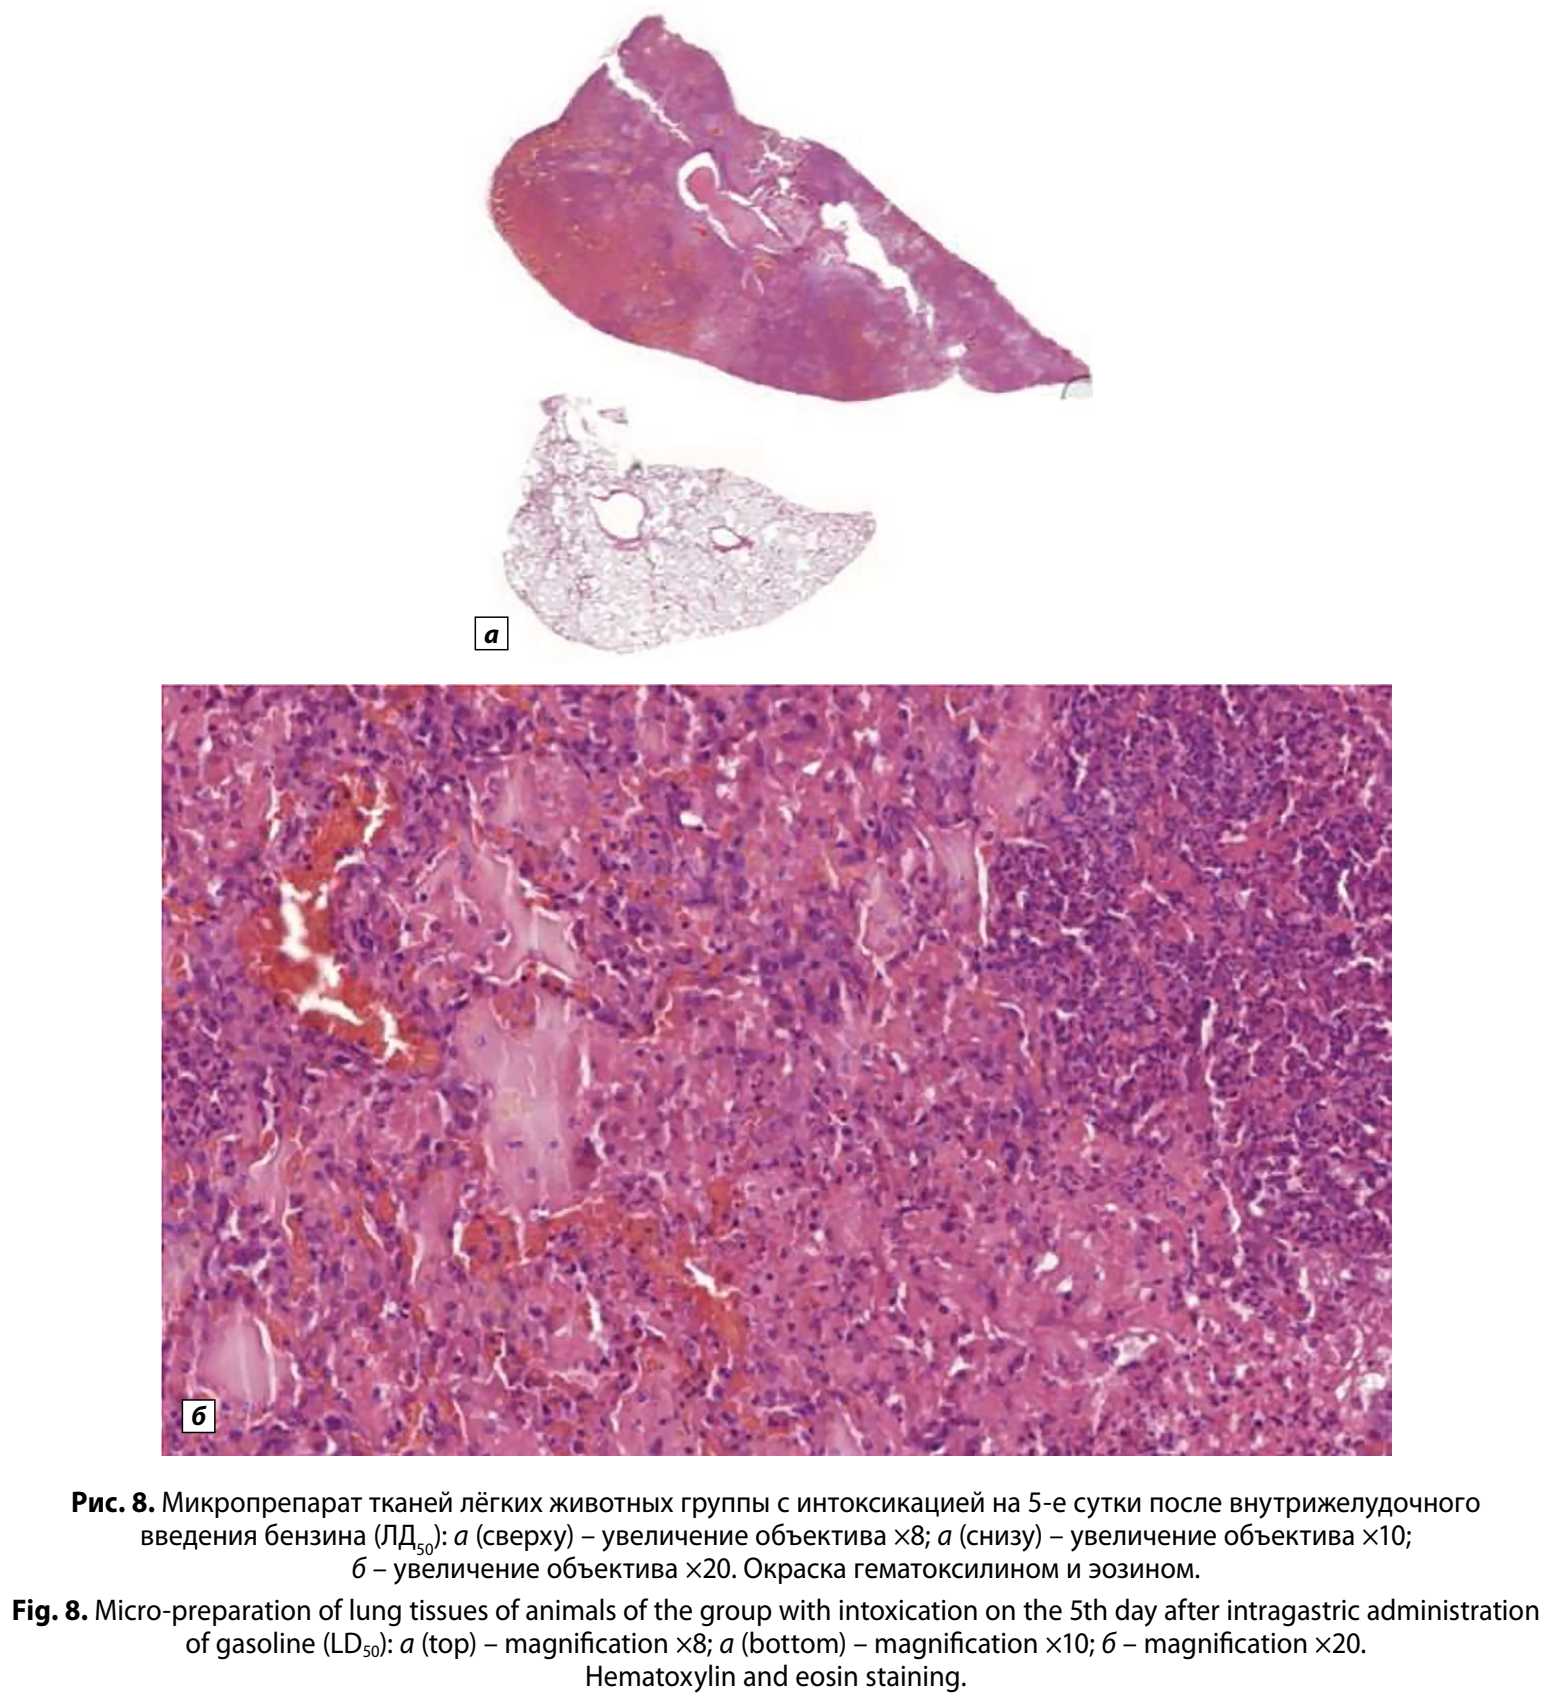

На 5-е сутки после воздействия в просвете бронхов и многих альвеолярных полостях обнаружили гнойный экссудат, нейтрофильную инфильтрацию межальвеолярных перегородок. В бронхах выявляли разрыхление, дезорганизацию, очаговую десквамацию и секвестрацию эпителия, что приводило к формированию гнойных масс, перекрывающих просвет альвеол и бронхиального дерева. По площади поражения лёгочной ткани изменения варьировали от очаговых до субтотальных. В долях с гнойно-некротическим пневмонитом перегородочные капилляры были сдавлены альвеолярным содержимым. В просветах сосудов мышечного типа идентифицированы тромбоцитарно-эритроцитарные тромбы, в центре которых визуализировали лизированные эритроциты с нечёткими контурами, что указывает на деградацию клеточных мембран. Реологические изменения крови были выражены в её делении в просвете сосудов на форменные элементы и плазму. Местами встречали многочисленные диапедезные экстравазаты. В сравнении с гистологическими препаратами лёгких, полученных на 1-е сутки после воздействия, выявленная эмфизема носила уже характер распространённого пневматоцеле. Выявили гранулематозную реакцию на липиды, окружённую соединительной тканью, фибробластами и лимфоцитами, образующими лимфатические фолликулы и пенистые макрофаги, заполненные оптически прозрачными везикулами (рис. 8, а, б, см. на вклейке).